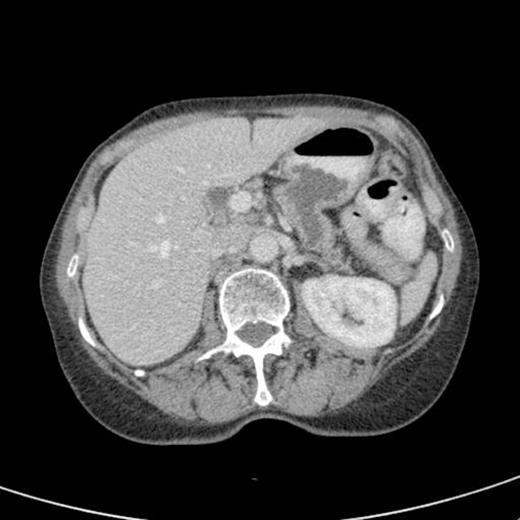

CT scan done at 10 years after initial diagnosis as part of routine surveillance revealed gross dilatation of main pancreatic duct to 10 mm along with a widely patent communication between the pancreatic duct and the stomach raising the possibility of a spontaneous gastro-pancreatic fistula measuring up to 19 mm associated with layering of mucin within the stomach. (Fig 3). The pancreas did not reveal any mass lesion and was globally atrophic. An upper GI endsocopy was done and this revealed a little crater with mucus plug in the body of the stomach along the lesser curve representing the opening of the gastropancreatic fistula. Biopsies taken around the fistula revealed non-specific inflammation. On clinic review, the patient complained of increased frequency of bowel habits, which was thought to be due to intestinal hurry caused by the fistula. This responded well to increased dose of creon.